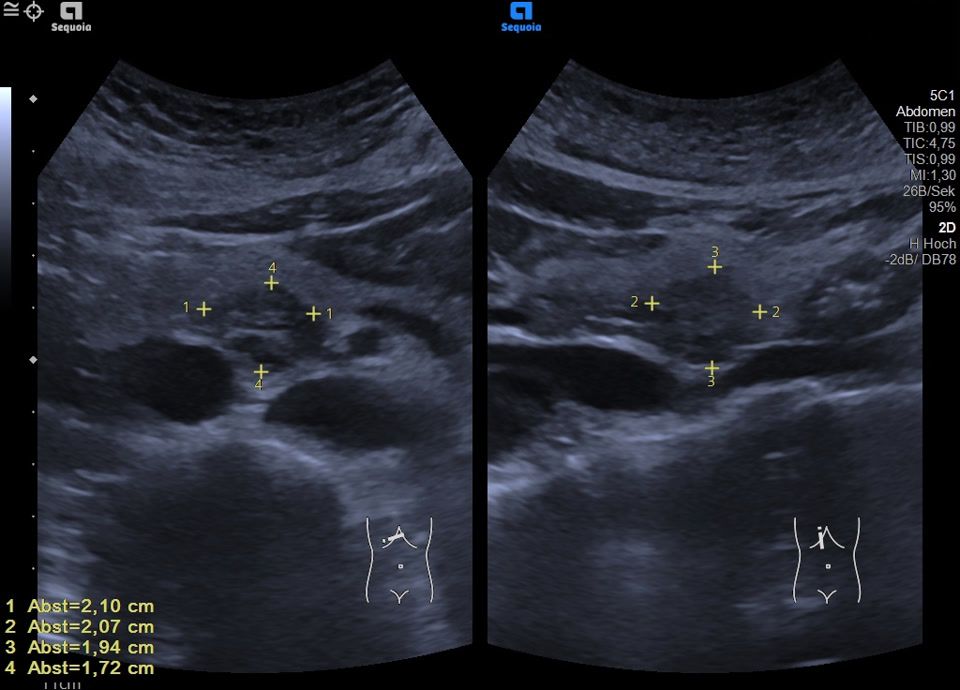

Case

60-year-old female patient with incidental finding of serous cystadenoma one year ago. Current follow-up examination reveals small cystic mass (honeycomb pattern visible on EUS) of constant size in the head of the pancreas/uncinate process. In the transcutaneous B-scan, central echogenic portion (central scar), hypervascularized on color Doppler sonography.